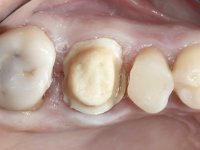

Teeth 17 and 16 were prepared for the fabrication of a 2-element Zr bridge. The impression was performed with a double mixing technique and a monolithic bridge in Zr was made in the laboratory. 4 years later, an abscess appeared in the apical area of tooth 26. It was decided to remove the bridge, remove the intra-radicular posts and retract the endodontic treatments of teeth 17 and 16. The removal of the bridge was carried out by making two cervical cavities. in the palatal area of the bridge and with a microluxator, disinsertion movements were performed. The intra-radicular posts were removed using fine drills and an ultrasound tip. The bridge was provisionally cemented and the patient was referred to a fellow endodontist for endodontic retreatment. After the retreatment, the intraradicular posts were placed again and the bridge was definitively cemented. One year later, a new abscess appears, possibly related to a root fracture. The bridge was sectioned between tooth 27 and 26 and tooth 26 was extracted and the crown of 27 was provisionally cemented. 3 months later, teeth 27 and 25 were prepared and a temporary bridge was made in dual polymerization resin. Then, an impression was made using the double mixing technique and a 3-element bridge in Zr was made in the laboratory. It was permanently cemented in the mouth with resin-reinforced glass ionomer cement.